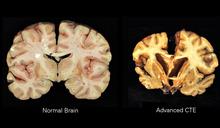

CTE is the current terminology used to describe the chronic, neurodegenerative brain disease that worsens over time caused by repeated trauma to the brain. Traumatic brain injuries (TBI) have been in the scientific literature with different names since the 1920’s.

CTE is caused by repeated blows to the head. Contact sports such as boxing and football traumatize the brain causing CTE symptoms. Any activity which forcefully and repetitively strikes the head can lead to this condition. The other aspect is the accumulation of the faulty, misshaped tau protein in the brain, which harms communications between neurons, the nerve cells in the brain.

Presently, the only definitive way to diagnose chronic traumatic encephalopathy is by post-mortem autopsy, The diagnosis of CTE requires the accumulation of Tau proteins that cluster around the brain’s blood vessels. This disease progresses to involve more areas of the brain with evidence of degeneration of brain tissue.